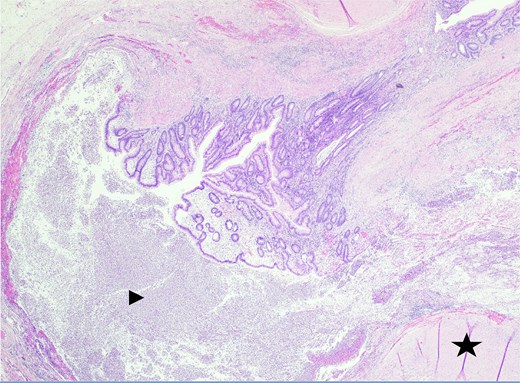

In the operating room, multiple adhesions from the patient’s prior colostomy site and colon resection were noted. The appendix was found to be dilated, acutely inflamed, and hyperemic, consistent with the suspected diagnosis of acute appendicitis. Adhesions from the appendix to the abdominal sidewall were dissected bluntly, pulling the appendix to a more medial position. The harmonic surgical device was used to divide the appendix mesentery and the gastrointestinal anastomosis (GIA) stapler with a blue load was used to divide the appendix from the base of the cecum. Final pathology showed an intact vermiform appendix measuring 6.5 × 1.5 cm with 3.2 × 2.5 × 1.6 cm portion of the attached mesoappendix. On gross examination, tan-pink hemorrhagic serosa with minimal adhesions and no exudate was noted. Sectioning of the specimen revealed a 0.5-cm in diameter lumen filled with a moderate amount of hemorrhagic purulent fecal material and at the distal tip, an intact diverticulum with wall measurement up to 0.2 cm in average thickness (Figs 1 and 2).

Sectioning of the intact vermiform appendix, top portion, showing the muscularis propria (star), muscularis mucosa (arrowhead), and colonic mucosa (arrow).